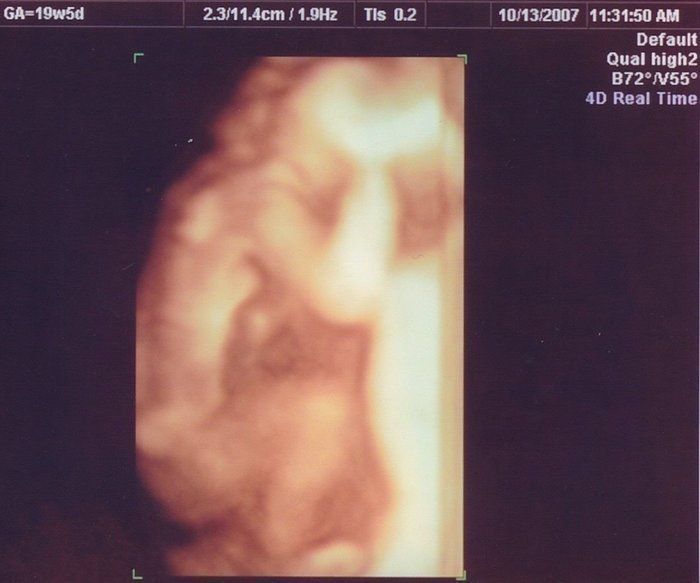

はやしなおさんの妊娠19週目のエコー写真 顔のパーツもエコーでわかるように

私が通う産婦人科では希望しない限りエコーは決められたときにしかなく、この日が久しぶりのご対面となりました。もうすっかり手足や顔のパーツが確認できるまでに成長し、赤ちゃんらしいシルエットになってきました。このころ長女の幼稚園通いが始まり、妊娠のために上の娘を積極的に外に遊びに連れて行ってあげられないジレンマは少し解消されました。幼稚園後、娘と遊んで過ごす時間を意識して、夕方から就寝の時間までに、たくさんのパワーを残しておくことを考えていました。